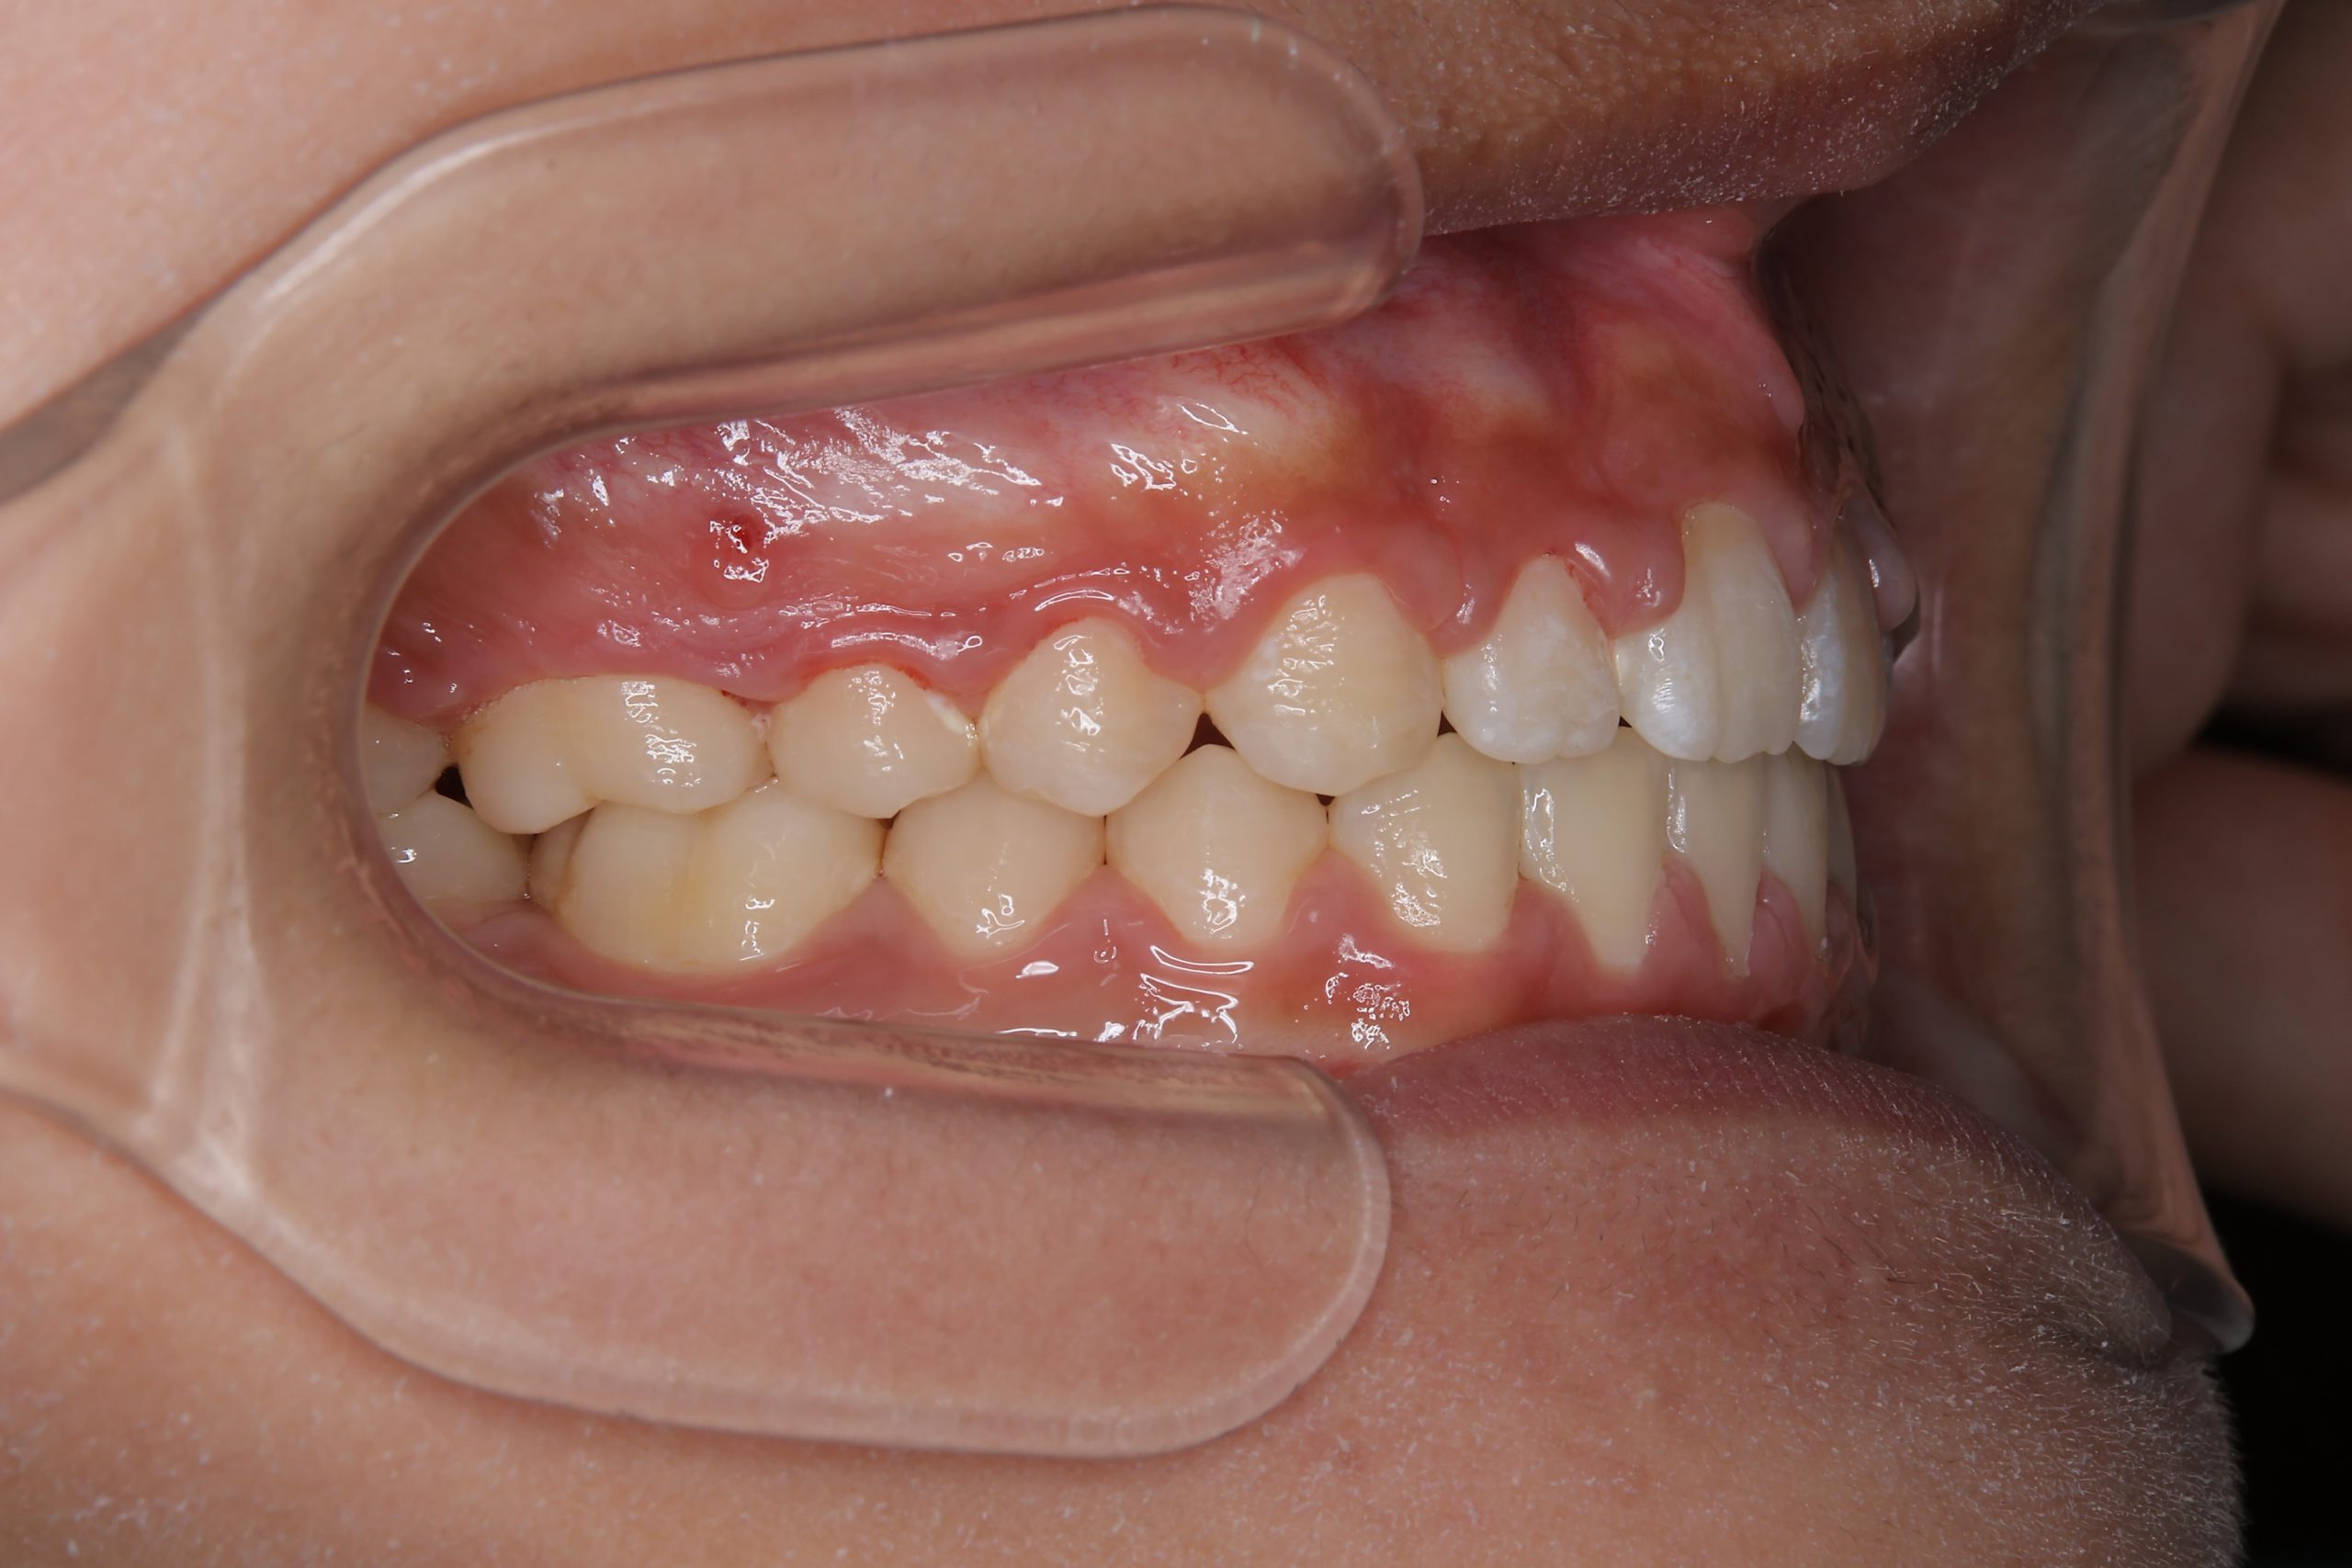

アフター

ワイヤー矯正治療|症例_681

主訴 上前歯が出ている|よく口が開いている

施術内容 上顎急速拡大装置と下顎リンガルアーチを用いて上下顎骨を拡大した。

その後マルチブラケット装置を用いて

非抜歯で歯牙を配列し良好な咬合を獲得した。

鼻閉症状は改善した。

治癒期間 2年10か月間